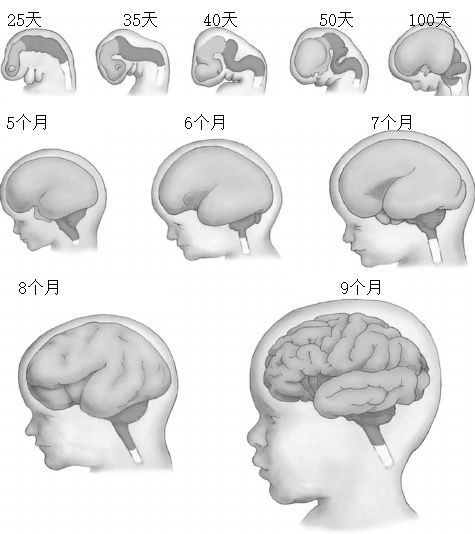

所以演化过程就另辟蹊径。因为皮质很薄,增加表面积就能增加它的数量,所以加入了很多折叠后,脑的体积基本不变,但是表面积能够增加几乎三倍。当胎儿还在子宫中 ,胎儿的大脑刚开始形成的时候,大脑是光滑的,大脑表面的折叠基本上是在孕期的最后两个月形成的。